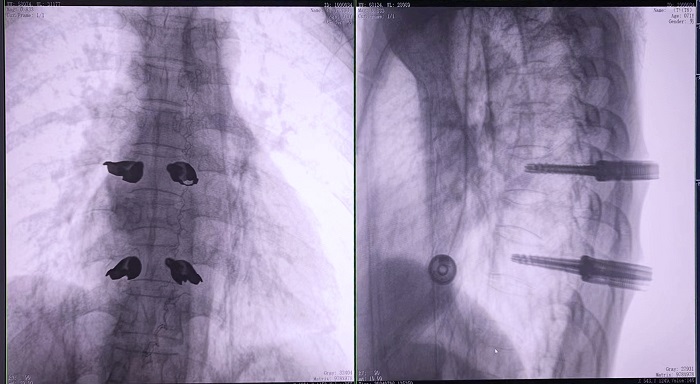

③機(jī)器人輔助胸椎手術(shù)操作難點(diǎn)之精準(zhǔn)置釘

傳統(tǒng)開放手術(shù)中,胸椎的手術(shù)視野相對(duì)受限,螺釘?shù)闹萌胫饕蕾囉卺t(yī)生的經(jīng)驗(yàn)和手感,存在一定的主觀性。

普愛醫(yī)療手術(shù)導(dǎo)航定位系統(tǒng)解決方案

普愛醫(yī)療骨科手術(shù)機(jī)器人的高精度機(jī)械臂,按照規(guī)劃好的路徑及角度,自動(dòng)精準(zhǔn)定位穿刺點(diǎn),醫(yī)生打入克氏針后,正側(cè)位圖像顯示精度滿足預(yù)期,醫(yī)生完成置釘?shù)群罄m(xù)手術(shù)操作。